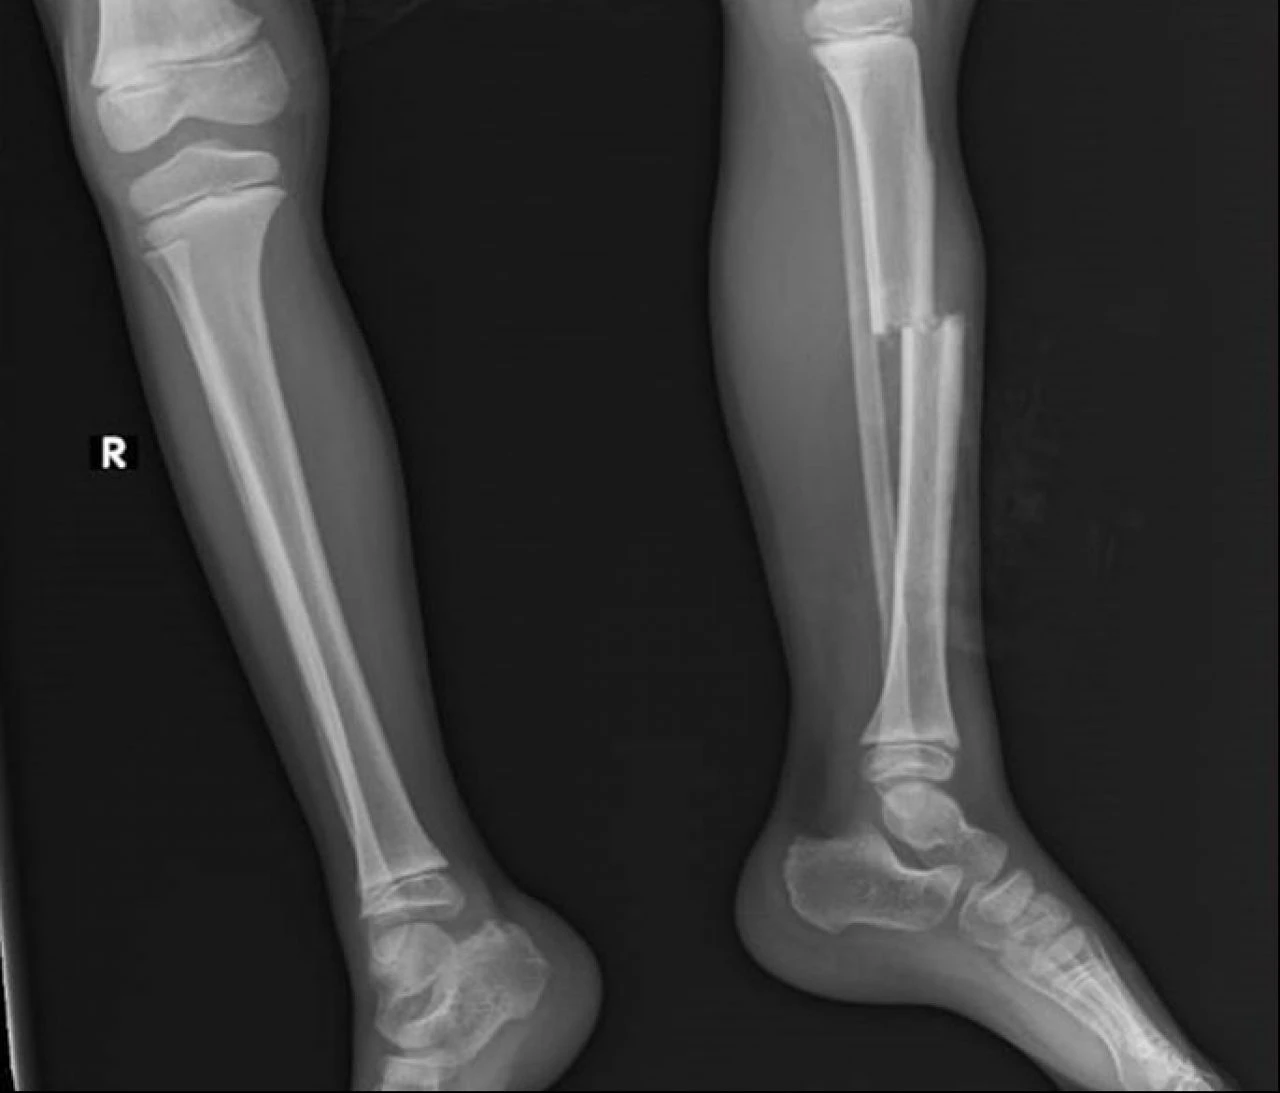

Diğer çocuklar kaçarak olayı yara almadan atlatırken, minik Eymen yaklaşık 1,5 metre yükseklikten düşüp, mermer ve beton parçaların altında kaldı. Diğer çocukların durumu bildirmesi üzerine olay yerine gelen anne Atiye Çiçek, çocuğunu kanlar içerisinde görünce büyük bir şok yaşadı. Sol bacak kaval kemiği kırılan, kafa ve vücudunun çeşitli noktalarında kesiler oluşan küçük Eymen, Kepez Devlet Hastanesinde tedavi altına alındı.